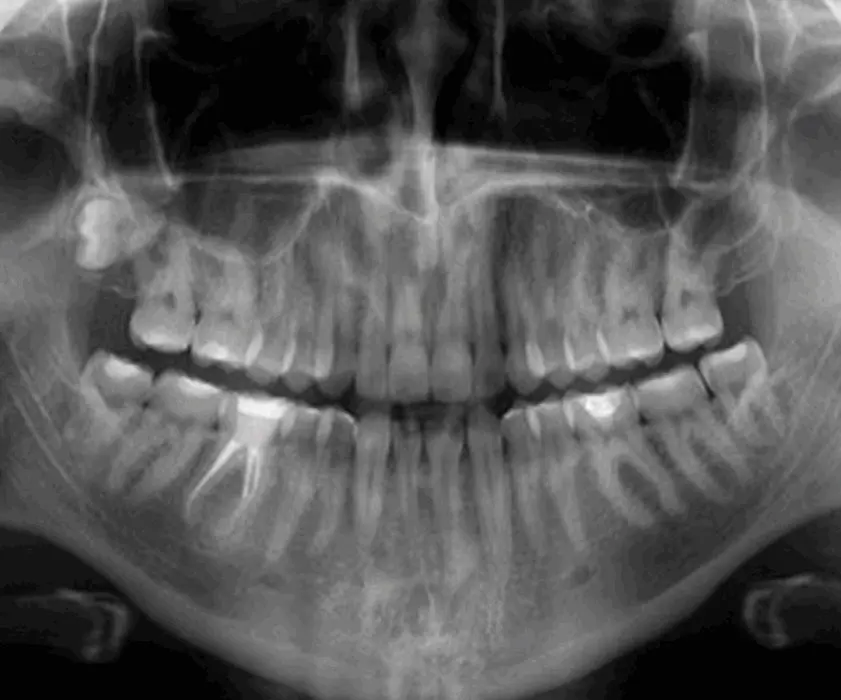

S panoramsko sliko je možno zelo hitro in jasno ugotoviti vzrok bolečine in otekline, na kar stomatolog lahko predlaga načrt terapije. V stomatološki polikliniki Štimac v Zagrebu, stomatolog Filip Štimac, specializant oralne kirurgije, vam bo natančno razložil poseg cistektomije ter kaj lahko pričakujete po posegu.

Zobne ciste so votline, obložene s tkivom in se lahko pojavijo v zobni čeljusti ali na mehkih tkivih (npr. v obrazu). Zobni ciste nastanejo kot posledica konstantne okužbe, ki se pojavlja na vrhu korenine. Do okužbe ponavadi pride zaradi slabe ustne higiene ali pa kariesa, ki ni pravočasno zdravljen. V primeru zobnih cist in drugih sindromov, je možen tudi vpliv genetike.

Če se diagnosticira ena izmed navedenih sprememb, jo je potrebno čimprej odstraniti, kakor ne bi rastla in se razširila na sosednje zobe. Brez zdravljenja sprememba lahko oslabi zobne strukture, poškoduje zdrave zobe, vpliva na sinus in nos in povzroči vnetija na obrazu. Cistektomija se opravlja pod lokalno anestezijo, kar pomeni, da je postopek popolnoma neboleč. Oralni kirurg med operacijo popolnoma odstrani cisto, skrajša vrh korenine in zapre zob. Če je cista zajela večji del korenine, je zob potrebno izdreti in odstraniti cisto. Teden dni po operaciji se odstranijo šivi.